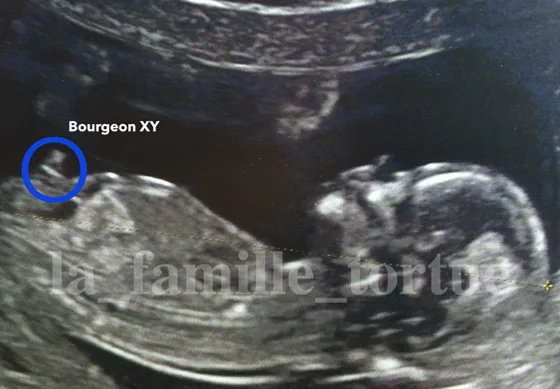

bourgeon-garcon-echographie-la-famille-tortue par la_famille_tortue | Avr 6, 2023 | 0 commentaires Laisser un commentaireAnnuler la réponse.